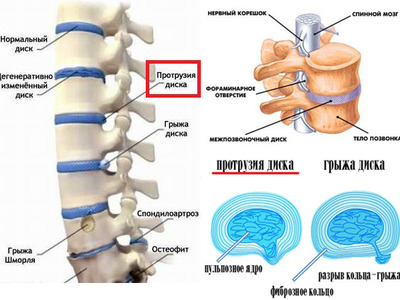

КТ-протрузии дисков: Визуализация и классификация